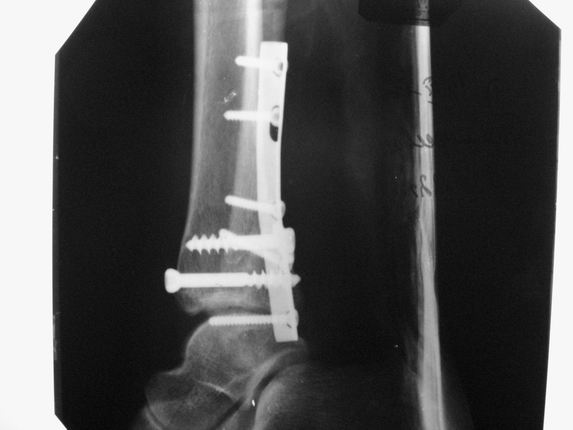

Re: Консолид. перелом г/ стопного

послал Алексей Минервин 16 Март 2006, 17:06

Уважаемые коллеги! Как и обещал, представляю плоды своей работы. Хвалиться особо нечем. Пошли задним

доступом сначала к м/берцовой кости, благодаря смещению линию перелома удалось сразу дифференцировать и по ней узким долотом (без молотка) мобилизовали отломки. Затем выделили задний край, там было проще пройти по линии перелома. Далее пластина по задней поверхности в дистальный отломок, винт проксимальнее пластины и дистрактором с трудом растянули отломки, ощущение было идеальной репозиции м/берцовой кости( доступен осмотр по задней и наружной поверхности), далее винты стандартно. Кстати, положение больной на боку: очень неудобно, но по-другому потом не повернуть на спину, чтобы сделать снимки в стандартных проекциях (ЭОПа нет). Затем дистрактор (два полукольца, спицы), репозиция заднего края, спонгиозный винт с шайбой, слишком проксимально, поэтому + еще один. Доступ к дельтовидной связке: рубец в передней порции, частично иссечен, шов. В общем, длительность операции 3,5 часа, а сказать, что все задуманное получилось, не могу.

А.Минервин.